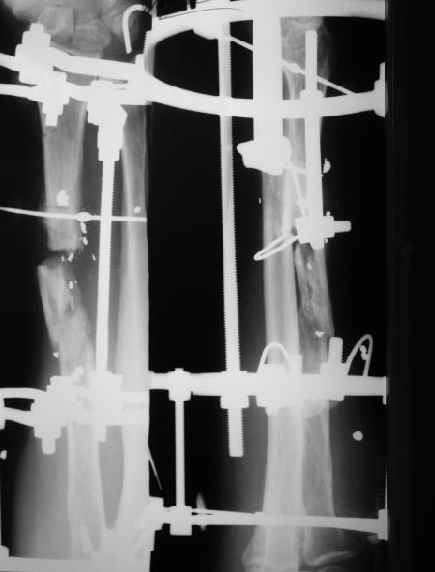

Дрягин Виталий 25 Апрель 2004, 16:32

Уважаемый Александр.Несколько поздно решил написать.При дефектах после любых повреждений мы предпочитаем аутопластику из малоберцовой кости по типу русского замка.Предплечье не нашел на рентгене,но зато нашел плечо.Я думаю Вы все поймете.С уважением .